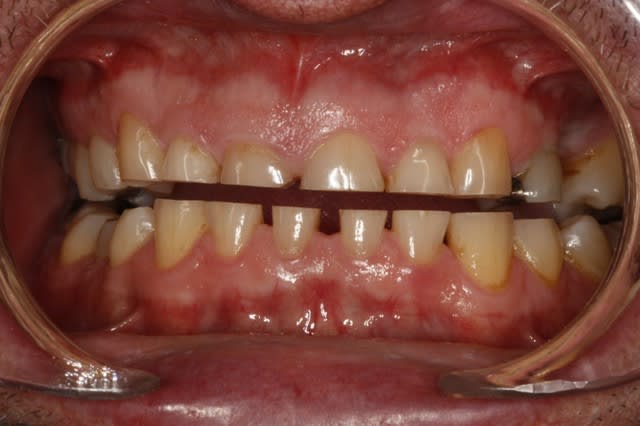

Tu penses quoi de ce patient, 50 ans.

Perte de DV ou non ?

Je restore comme cela ou bien je dois ouvrir 1-2 mm ?

Je laisse comme cela ?

--

Céramik